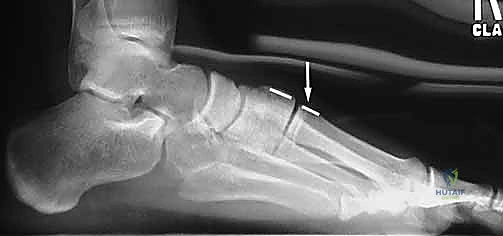

الأشعة السينية العادية قد لا تظهر الإصابة إذا لم تكن العظام مزاحة بشكل كبير. السر يكمن في طلب أشعة سينية أثناء وقوف المريض وتحميل وزنه على القدم المصابة (Weight-bearing X-rays).

* يبحث الدكتور هطيف عن "علامة الفليك" (Fleck Sign)، وهي قطعة عظمية صغيرة مكسورة ومسحوبة من قاعدة المشط الثاني أو العظم المسماري الإنسي، وهي دليل قاطع على تمزق رباط ليزفرانك.

* كما يتم قياس المسافة بين قاعدة المشط الأول والمشط الثاني. أي اتساع يزيد عن 2 ملم يُعتبر غير طبيعي ويشير إلى عدم الاستقرار.

4. التثبيت (Fixation): يتم تثبيت العظام باستخدام مسامير معدنية خاصة (Solid or Cannulated Screws) تعبر المفاصل لتثبيتها بإحكام. في بعض الحالات، يتم استخدام شرائح معدنية صغيرة للحفاظ على الاستقرار.

5. مسمار ليزفرانك: الخطوة الأهم هي وضع "مسمار ليزفرانك" (Lisfranc Screw) الذي يمر من العظم المسماري الإنسي إلى قاعدة المشط الثاني، لتعويض وظيفة الرباط الممزق.